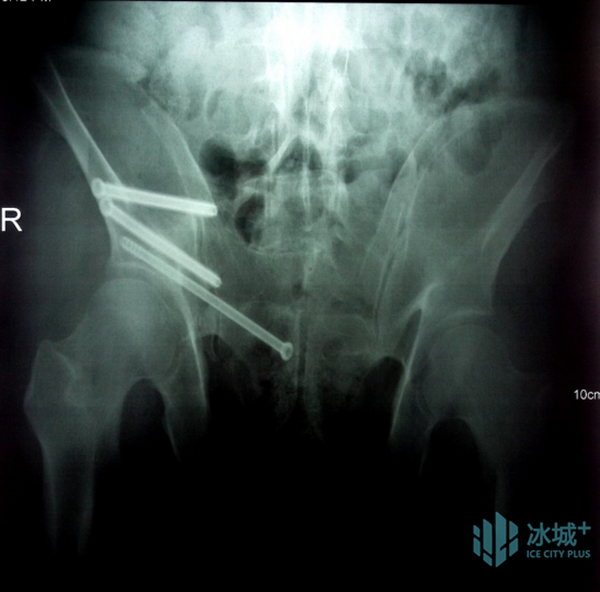

术中透视验证螺钉置入效果

术中,刘建宇教授对复位位置及路径进行预览并确认规划后,分别将手术机械臂与患者健侧、患侧稳定固定把持,并使用电动骨科牵引架与患者下肢稳定连接,采用力-位协同控制模式进行机器人精准闭合复位,在全程多角度实时可视监控和自动规划引导下,安全完成骨盆骨折闭合复位,术中透视验证复位结果满意。最后,他操作机器人进行了螺钉通道置入规划,在实时动态三维可视化导航下,精准置入螺钉,完成了该例骨盆骨折的微创治疗。“数智化微创手术”用时2小时,患者腹部仅留有5个长度1cm的手术切口,术中出血量仅有50ml。